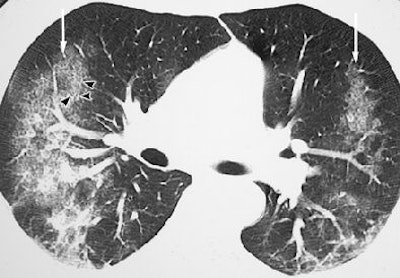

These are your lungs on crack

On x-rays, acute lung injury after cocaine use can appear as "bilateral, perihilar areas of increased opacity or attenuation, usually without pleural effusion or cardiomegaly," according to Dr. Michael Gotway and colleagues from San Francisco General Hospital; the University of California, San Francisco; and Brigham and Women's Hospital in Boston. "High-resolution CT may show multifocal ground-glass attenuation associated with septal thickening," but the condition clears up quickly after discontinuing cocaine use, they reported (RadioGraphics, October 2002, Vol. 22:4, pp. S119-S135).

| Acute lung injury (crack lung) in a 37-year-old man who presented with shortness of breath and cough after crack use. Above, frontal chest radiograph reveals ground-glass areas of increased opacity in the right lower lobe (arrow), a finding that is consistent with numerous causes, including edema, infection, hemorrhage, and aspiration. Below, high-resolution CT scan (level = -700 HU, window width = 1,000 HU) reveals ground-glass attenuation (arrows) with interlobular septal thickening (arrowheads). The differential diagnosis of these findings includes infection (especially Pneumocystis carinii pneumonia), lipoid pneumonia, and alveolar proteinosis, among numerous other causes. Bottom, frontal chest radiograph obtained two days after CT shows resolution of the increased opacity. Fig. 3a, b, c. Gotway MB, Marder SR, Hanks DK, et al. "Thoracic Complications of Illicit Drug Use: An Organ System Approach." RadioGraphics. 2002;222:S119-S135. |